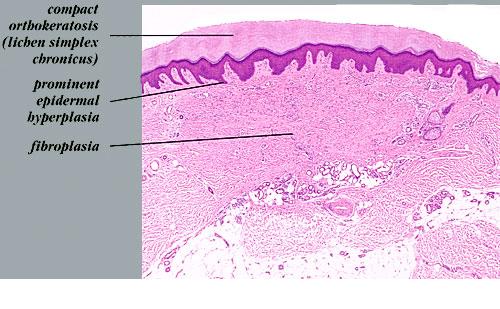

The overlying epidermis is usually acanthotic. Pseudoepitheliomatous hyperplasia and a basaloid proliferation may be noted. The hyperplasia may be caused by the action of fibroblasts on epidermal keratinocytes.23  Basal cell carcinomas occurring upon a dermatofibroma have been reported. Increased pigment may be seen, which may be iron or melanin. Most lesions display a grenz zone of normal papillary dermis overlying the tumor.

The bulk of the tumor is within the mid dermis where no capsule is present and the periphery of the lesion blends with the surrounding tissue. Whorling fascicles of a spindle cell proliferation with excessive collagen deposition are characteristic. At the periphery, the spindle cells characteristically wrap around normal collagen bundles (see the images below). Occasionally, melanocytes have been reported to be interspersed amongst the spindle cells.24